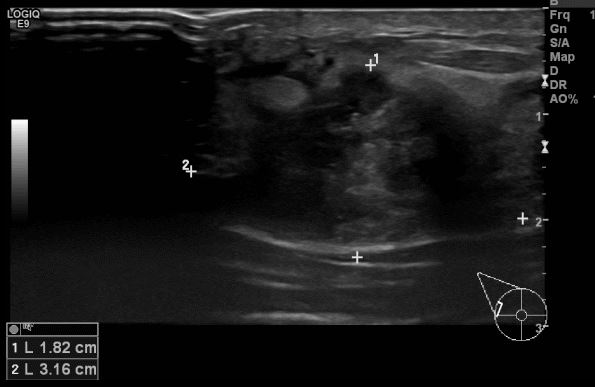

상기환자 건강검진상 이상소견으로 내원하신 40대 여성분으로 우측 상외측 장경 3.16cm  의심스러운 멍울 조직검사 시행하여 우측 침윤성 유관암 진단 되었습니다.